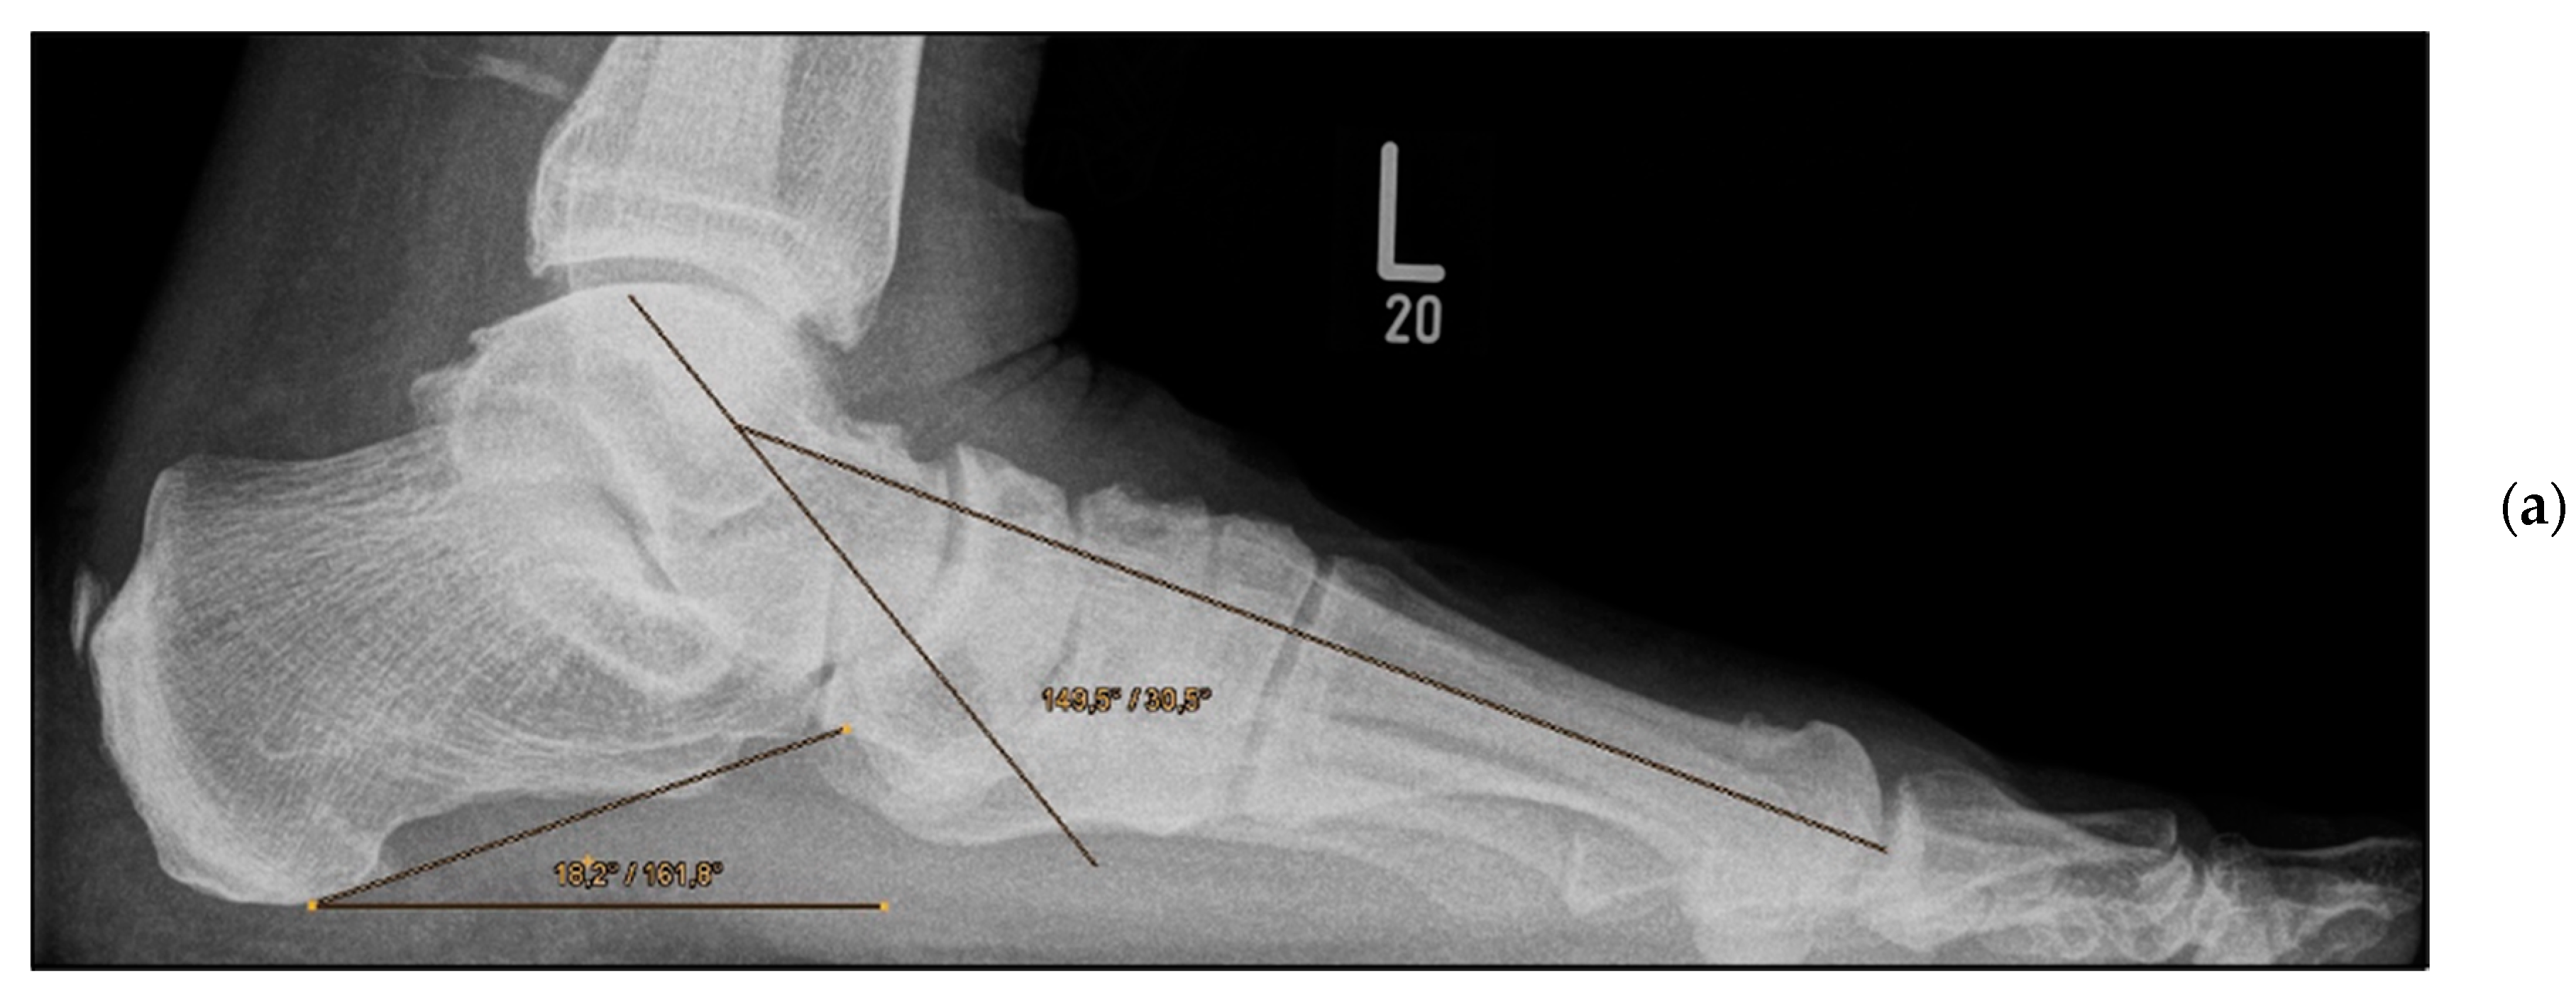

Pre- and post-operative radiographic findings of double arthrodesis, left foot. (a) Anteroposterior view pre-operative, (b) anteroposterior view post-operative.

Figure 5.

Double Arthrodesis (Group B). Firstly, subtalar arthrodesis was performed via a lateral subtalar approach. Care was taken to ensure thorough resection of the articular surfaces and extensive release to achieve adequate correction of the valgus deformity and avoid the development of pseudarthrosis. Here, too, the insertion of autologous cancellous bone was considered obligatory. Fixation was achieved by means of two percutaneously inserted lag screws (diameter of 6.5 mm). The subsequent talonavicular arthrodesis was performed as previously described (Figure 4a,b and Figure 5a,b).